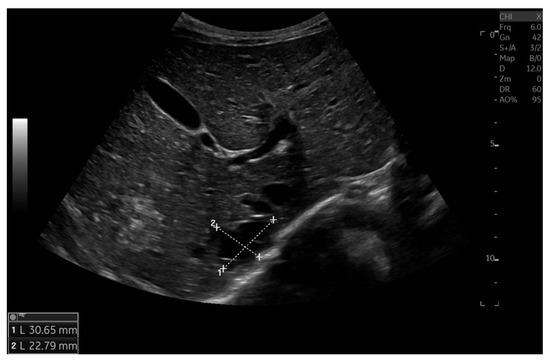

Currently, the boy is 5 years old. The US is similar to the previous one: elevated kidneys length (right: 130 mm (z-score 6.19); left: 133 mm (z-score 6.50)), with increased echogenicity, blurred corticomedullary differentiation, and multiple cysts with a maximum diameter up to 13–15 mm. The liver has a normal size, with numerous cysts up to 16 mm in diameter, with the largest cluster of cysts measuring 43 × 23 × 31 mm (Figure 3 and Figure 4). Laboratory tests show increased creatinine 0.79 mg/dL, urea 69,6 mg/dL, cystatin C 1.71 mg/L, uric acid 6.9 mg/dL, urine albumin to creatine ratio (ACR) 118.6 mg/g, and decreased GFR 55 mL/min/1.73 m2—stage III CKD. Other tests, including electrolytes, liver function, and urinalysis, were normal. The boy demands antihypertensive multi-drug therapy: angiotensin-converting enzyme inhibitors (ACEIs), calcium channel blockers, and beta-blockers.

Figure 4. Ultrasonography of the liver with the largest cluster of cysts.